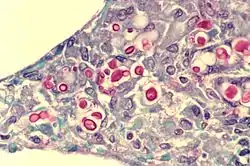

| Yeast state of Cryptococcus neoformans | |

Cryptococcus neoformans typically grows as a yeast (unicellular) and replicates by budding. It makes hyphae during mating, and eventually creates basidiospores at the end of the hyphae before producing spores. Under host-relevant conditions, including low glucose, serum, 5% carbon dioxide, and low iron, among others, the cells produce a characteristic polysaccharide capsule.[6] The recognition of C. neoformans in Gram-stained smears of purulent exudates may be hampered by the presence of the large gelatinous capsule which apparently prevents definitive staining of the yeast-like cells. In such stained preparations, it may appear either as round cells with Gram-positive granular inclusions impressed upon a pale lavender cytoplasmic background or as Gram-negative lipoid bodies.[7] When grown as a yeast, C. neoformans has a prominent capsule composed mostly of polysaccharides. Under the microscope, the India ink stain is used for easy visualization of the capsule in cerebral spinal fluid.[8] The particles of ink pigment do not enter the capsule that surrounds the spherical yeast cell, resulting in a zone of clearance or "halo" around the cells. This allows for quick and easy identification of C. neoformans. Unusual morphological forms are rarely seen.[9] For identification in tissue, mucicarmine stain provides specific staining of polysaccharide cell wall in C. neoformans. Cryptococcal antigen from cerebrospinal fluid is thought to be the best test for diagnosis of cryptococcal meningitis in terms of sensitivity, though it might be unreliable in HIV-positive patients.[10]